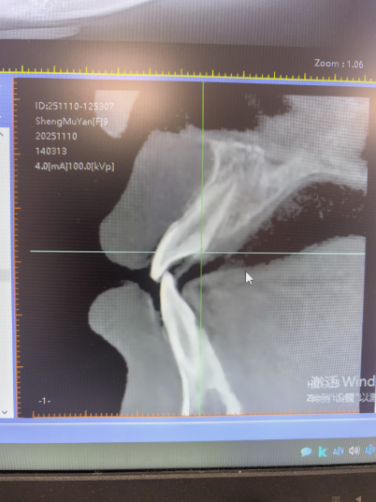

(要闻8)9 岁女童“地包天” 早期矫治见成效

近期,一名9岁女童“地包天”早期矫治显成效——通过混合牙列阶段的精准干预,不仅解决了咬合问题,更实现了面型的美观蜕变。

我院口腔中心医生提醒家长:若发现孩子咬合或面型异常,应尽早就诊,抓住生长发育关键期实现“颜值与功能”的双重改善。